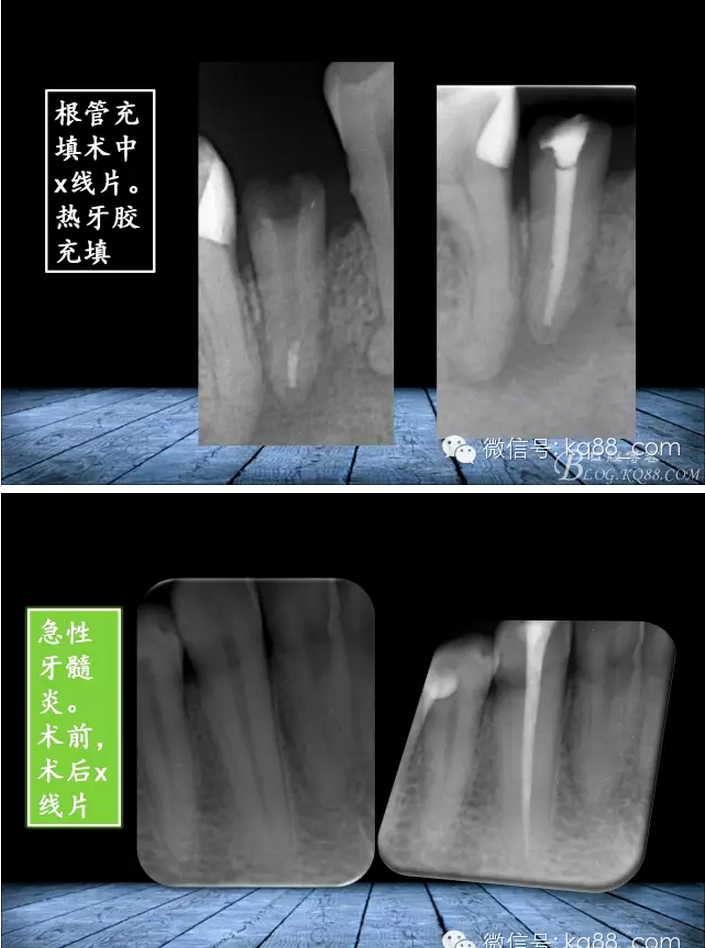

QQ圖片20150817140811.png

QQ圖片20150817140835.png